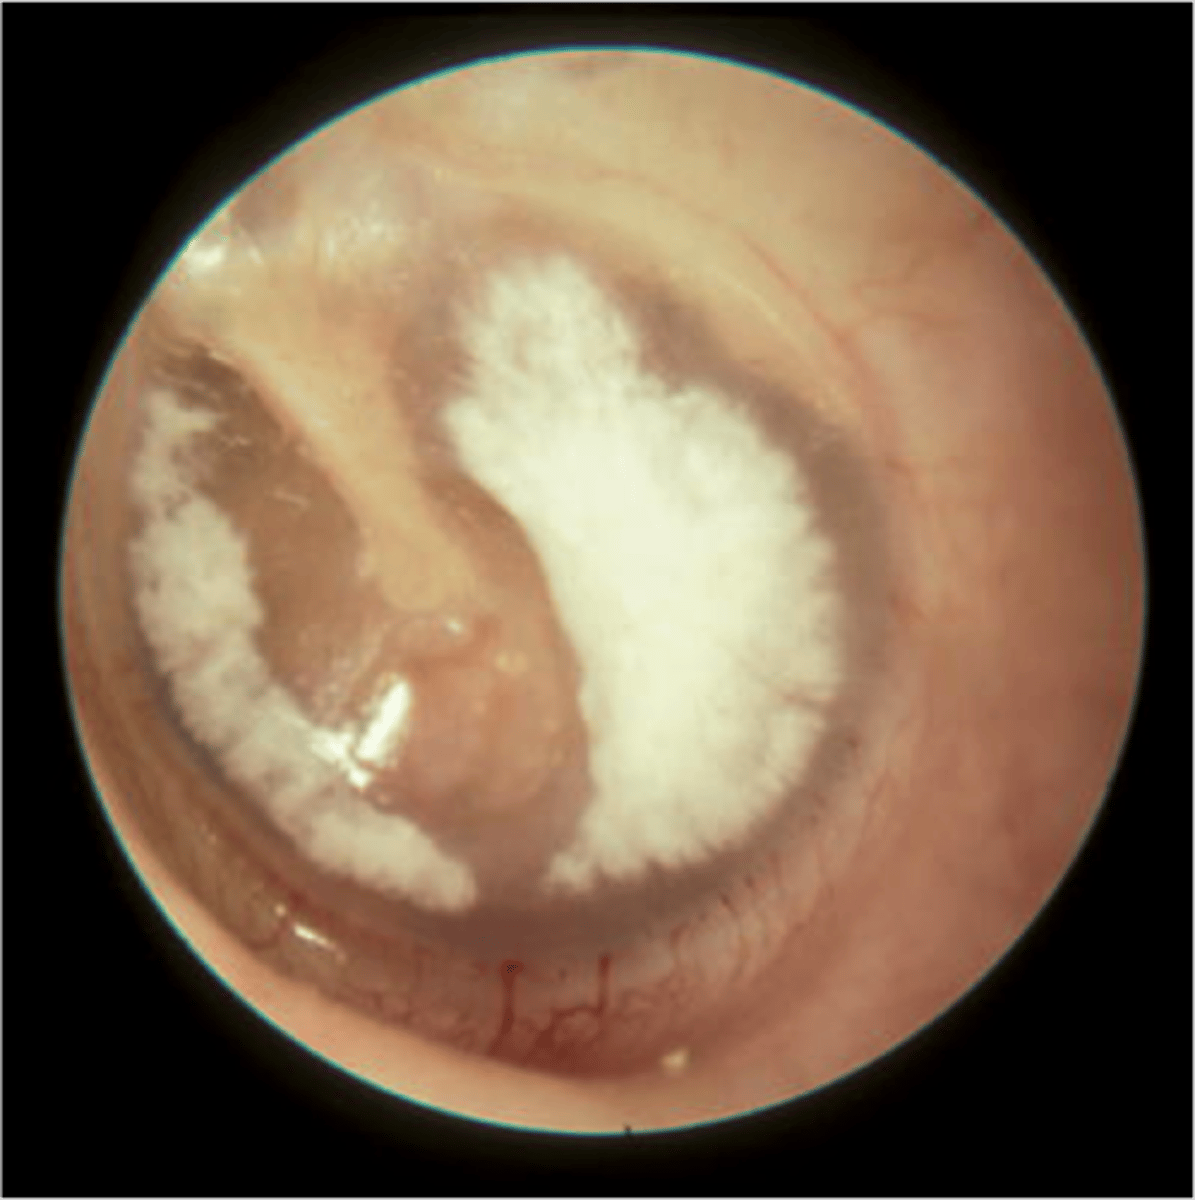

Tympansclerosis

white scarring on TM dt ear infection/ear tubes

<p>white scarring on TM dt ear infection/ear tubes</p>